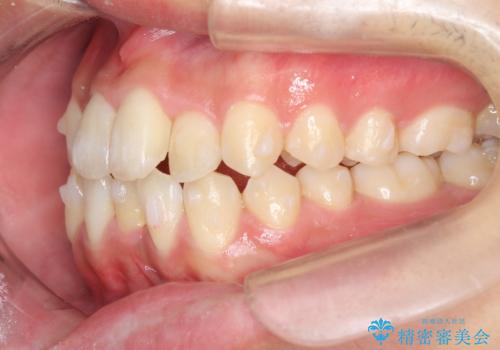

治療も順調に進み、リファインメントも1回のみで済んでいます。

ブラックトライアングルも少なめで、短期間でしっかり並びました。

下の前歯の歯槽骨が一番薄く、歯肉退縮のリスクがあるため、今回のような1本抜歯も選択肢の一つです。

上の前歯のガタガタも、わずかに歯を削って並べていますので、出っ歯になったりしないようにしています。